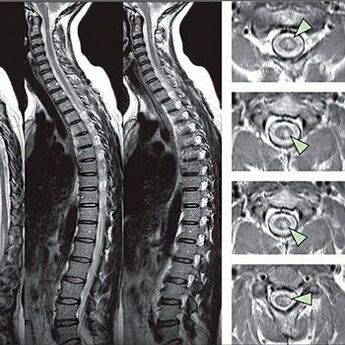

Vengono eseguiti test di funzionalità speciali per identificare i segni dei disturbi di sensibilità. L'opzione più informativa per la diagnosi dai metodi strumentali è l'esecuzione di un raggio X. Tuttavia, la risonanza magnetica e la TC sono spesso effettuati per un esame approfondito della colonna vertebrale. In caso di sospette malattie del sistema cardiovascolare, si raccomanda al paziente di sottoporsi alla procedura ECG.